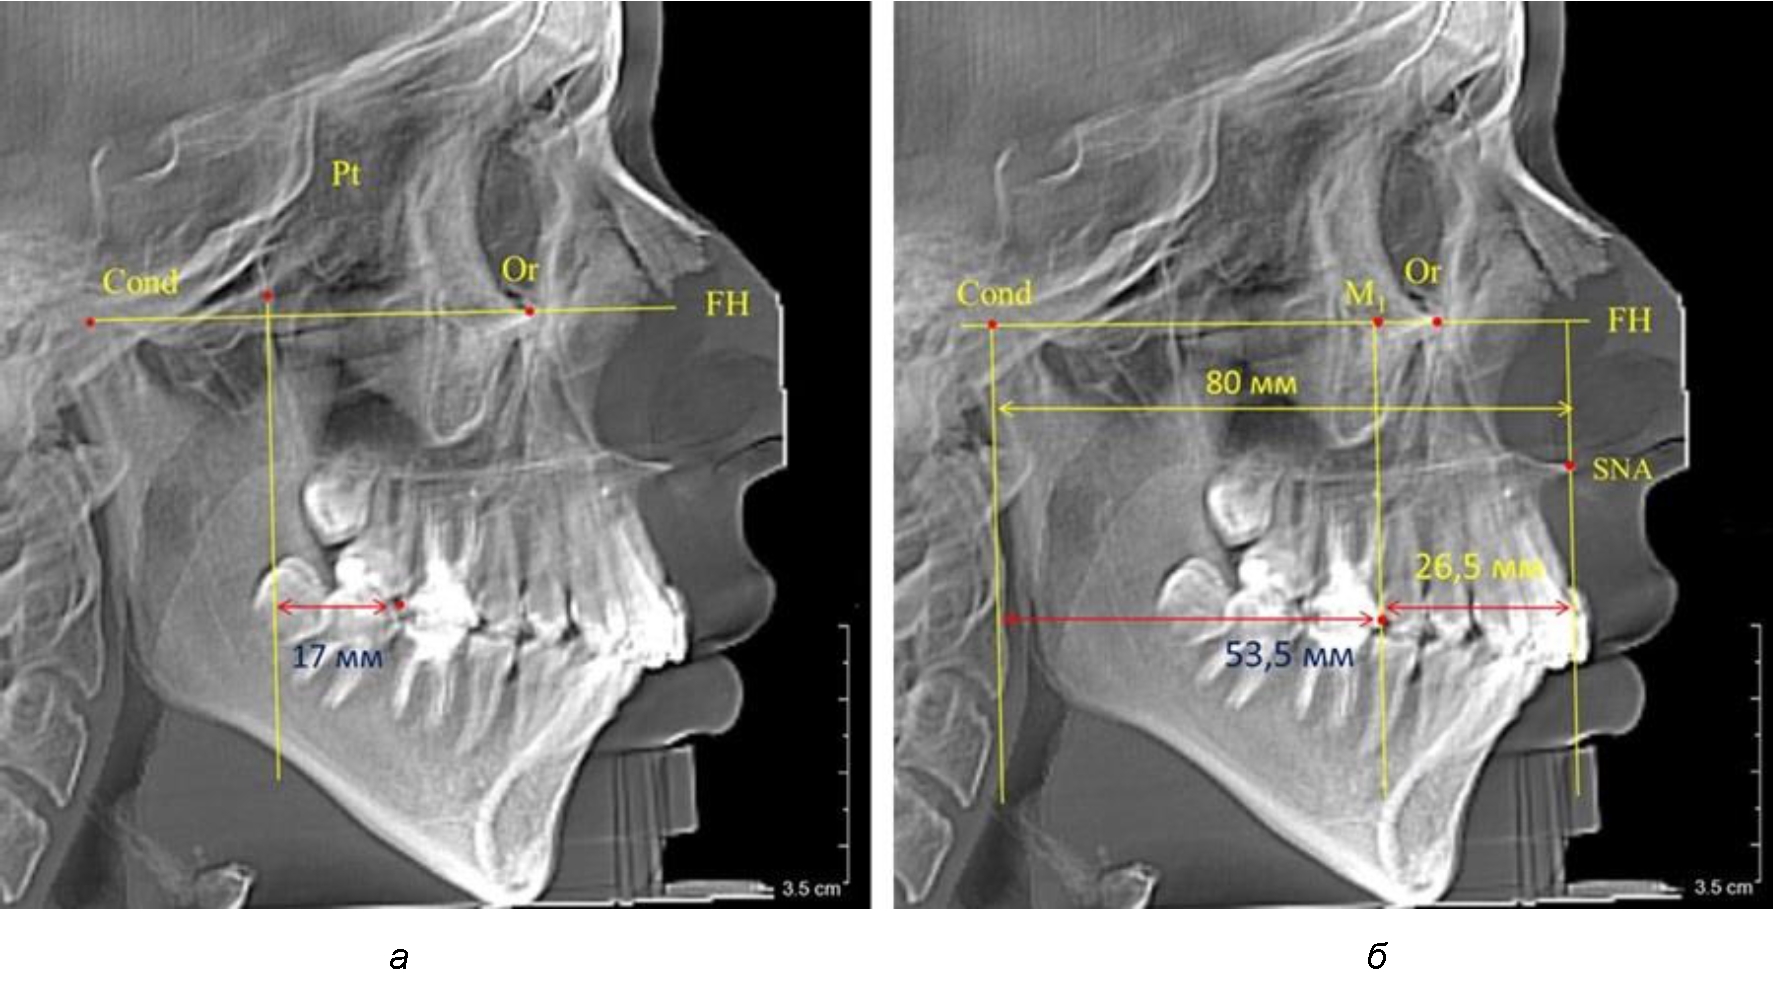

При проведении анализа к Франкфуртской горизонтали проводили передний и задний перпендикуляры. Передний спинальный перпендикуляр проходил через выступающую точку передней носовой ости (spina nasalis anterior – SNA), а задний суставной перпендикуляр опускали из кондилярной точки Cond. Молярный перпендикуляр проводили через медиальную поверхность первого постоянного моляра. Указанная вертикаль отделяла замещающие зубы постоянного прикуса от добавочных зубов (постоянных моляров), что вполне логично для анализа положения первых постоянных моляров в гнатическом комплексе (рис. 1).

Рис. 1. Метод определения положения первых верхних моляров по Ralph E. McDonald (а) и по предложенному методу (б)

Анализ проведенного исследования рентгенограмм показал существенную вариабельность практически всех линейных показателей. У молодых людей с физиологическим прикусом постоянных зубов расстояние от крыловидной вертикальной плоскости PTV до дистальной поверхности верхнего первого постоянного моляра в целом по группе составляло (18,37 ± 3,62) мм. Обращает на себя внимание большая ошибка репрезентативности из-за разницы между максимальными и минимальными значениями.

Среди анализируемых рентгенограмм минимальное значение расстояния по методу R. E. McDonald было 12 мм, а максимальное достигало 25 мм, что, по нашему мнению, обусловлено вариабельностью сагиттального размера гнатического отдела лица.

Среднее расстояние между суставной (кондилярной) и спинальной вертикалями в анализируемой группе составило (89,12 ± 2,8) мм. При этом сагиттальный размер в среднем составлял (58,74 ± 1,57) мм, а передний размер был (30,41 ± 1,02) мм. Несмотря на вариабельность размеров и большую ошибку репрезентативности, относительно стабильным показателем было отношение сагиттального размера гнатического комплекса к заднему отделу, которое составляло в среднем 1,5 ± 0,06.

Таким образом, для прогнозирования оптимального положения первых постоянных моляров наиболее целесообразным методом явилось использование относительного показателя, что подтверждено при анализе рентгенограмм с минимальными и максимальными значениями по методу R. E. McDonald.

Так, при расстоянии от крыловидной вертикальной плоскости PTV до дистальной поверхности верхнего первого постоянного моляра в 13 мм сагиттальный размер гнатического отдела был 82 мм. При этом отношение кондилярно-спинального расстояния к кондилярно-молярному размеру (54,5) было близким к коэффициенту 1,5, что представлено на рис. 2.

В то же время при увеличенном расстоянии от крыловидной вертикальной плоскости PTV до дистальной поверхности верхнего первого постоянного моляра, равное 23 мм, сагиттальный размер гнатического отдела составил 92 мм. При этом отношение кондилярно-спинального расстояния к кондилярно-молярному размеру (30,5), так же, как и при малых размерах, было близким к коэффициенту 1,5, что представлено на рис. 3.